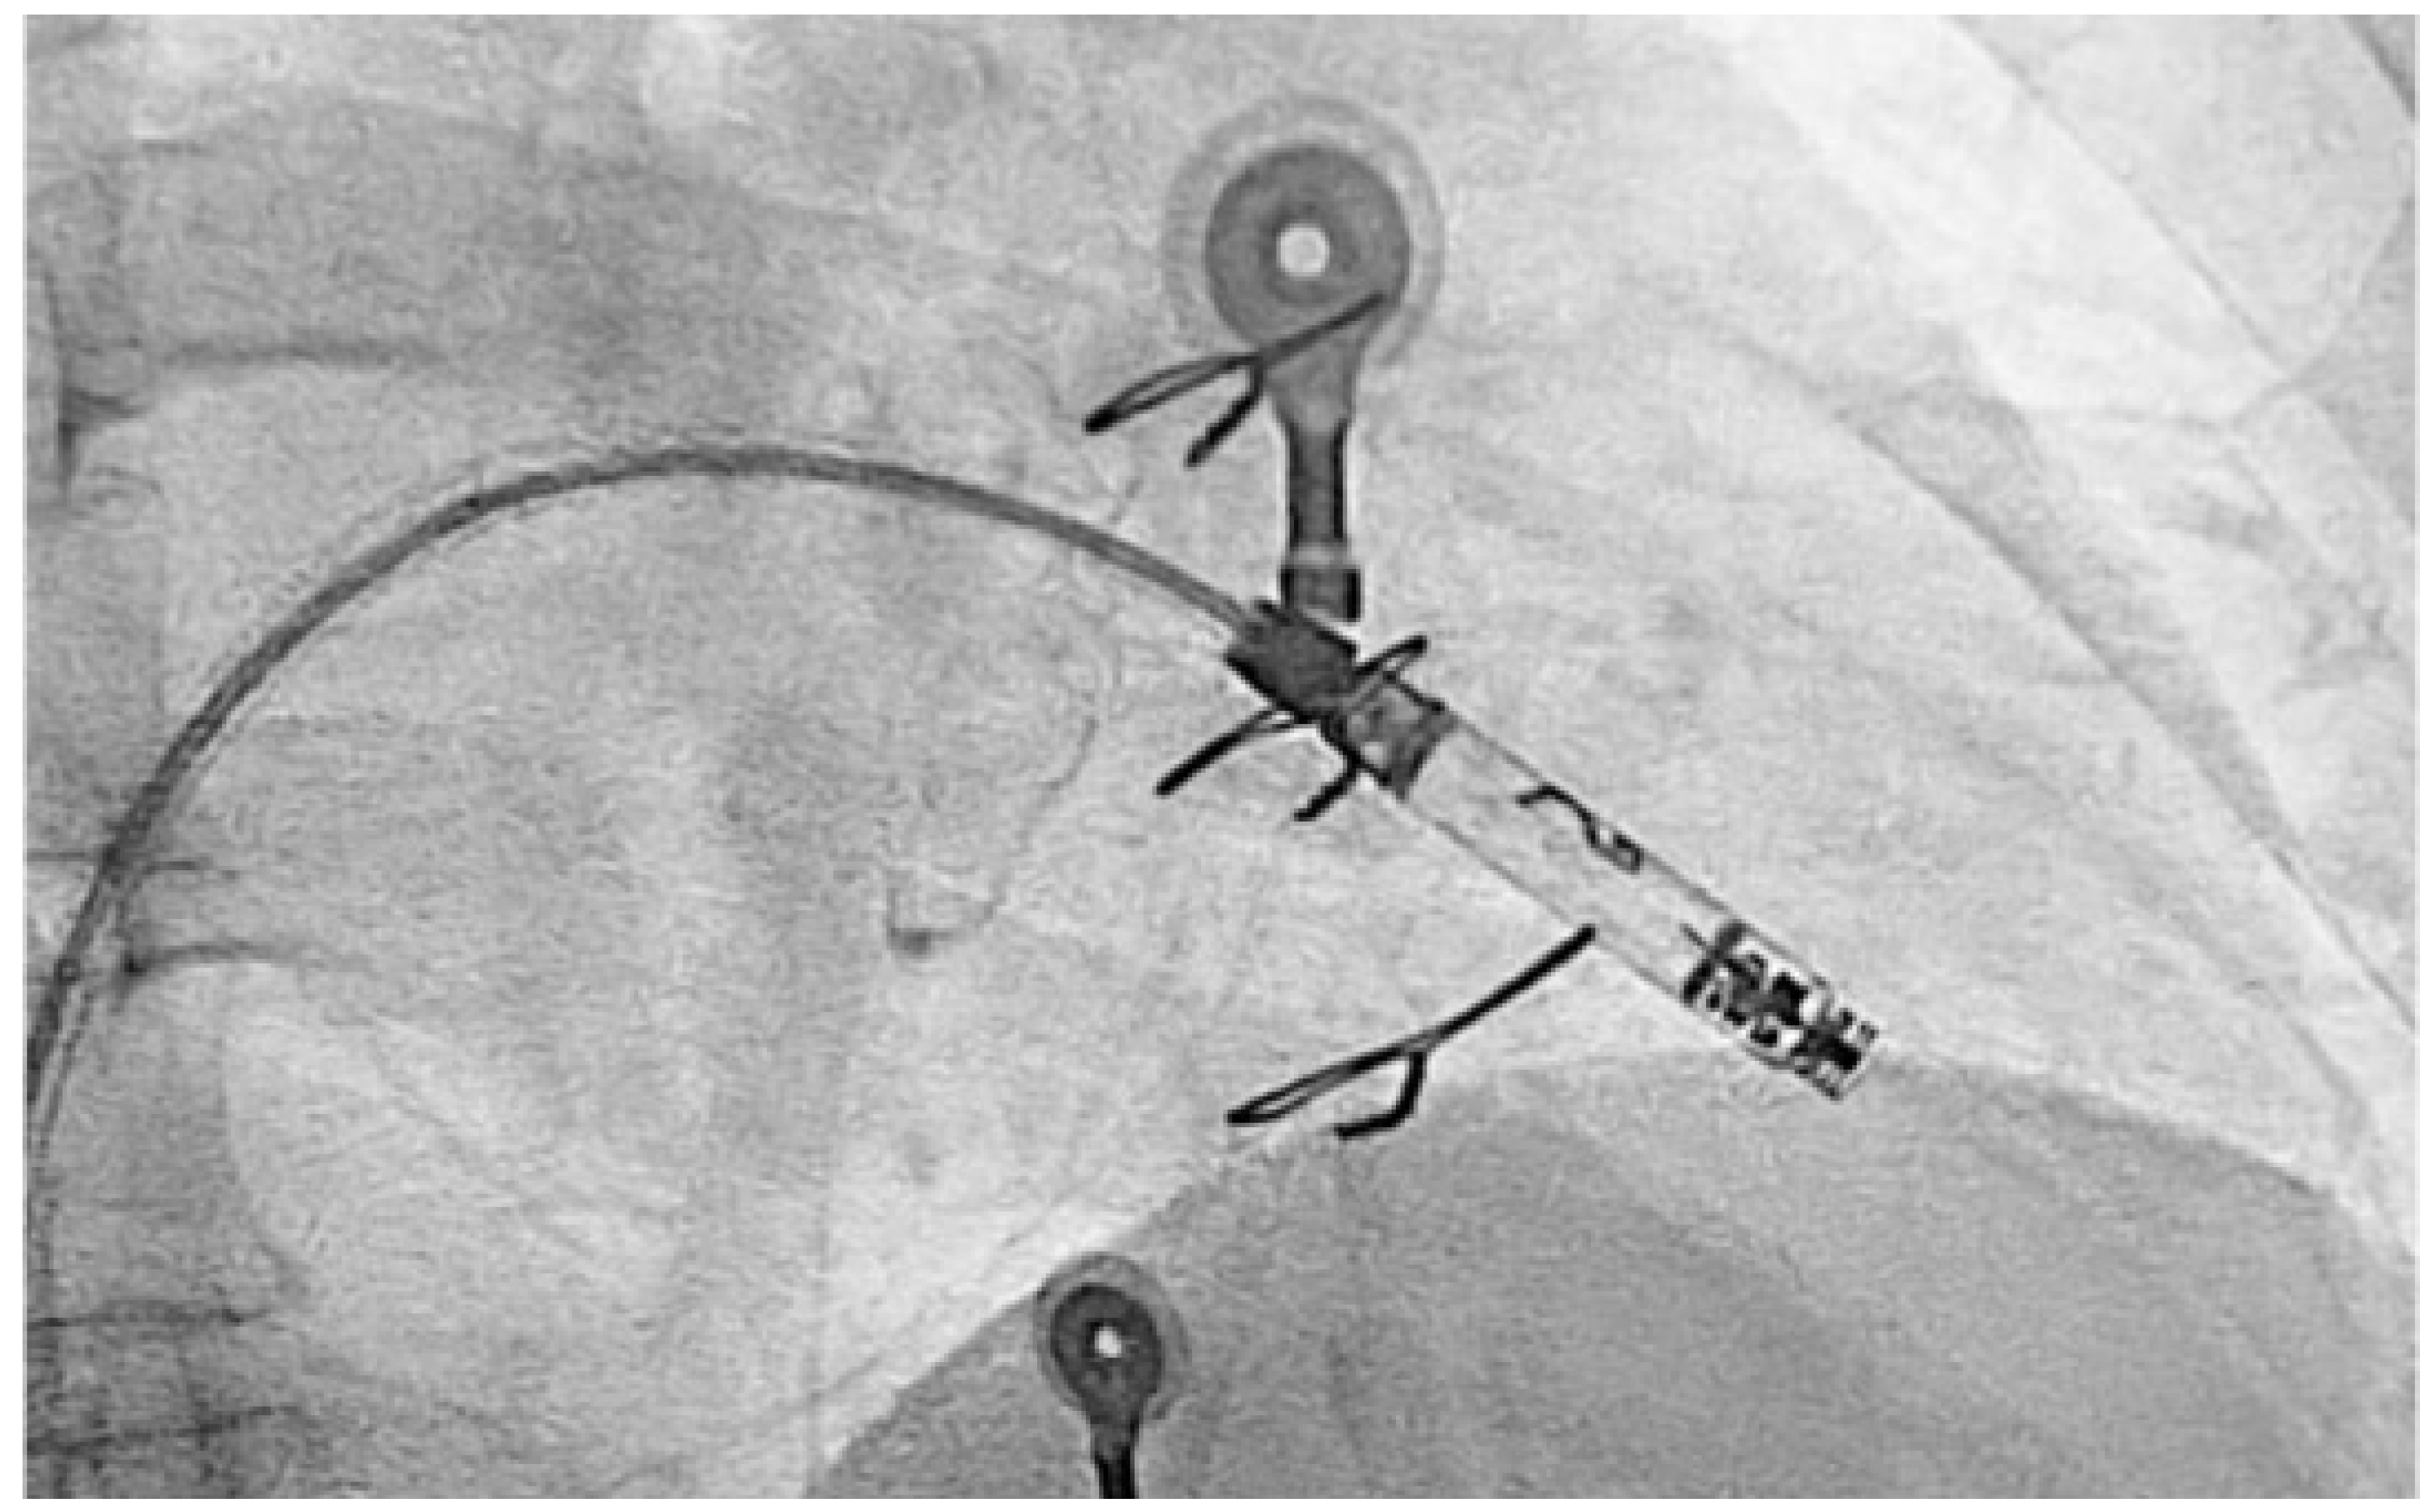

Due to recurrence of conduction disturbances and syncope, a leadless ventricular pacemaker (Aveir, Abbott) was implanted (Figure 5), and beta-blocker therapy was continued for rate control.

Figure 5. Fluoroscopic image showing the deployment of leadless ventricular pacemaker in the right ventricle via femoral venous access. The delivery catheter and fixation tines are visible, ensuring secure attachment to the endocardial surface.